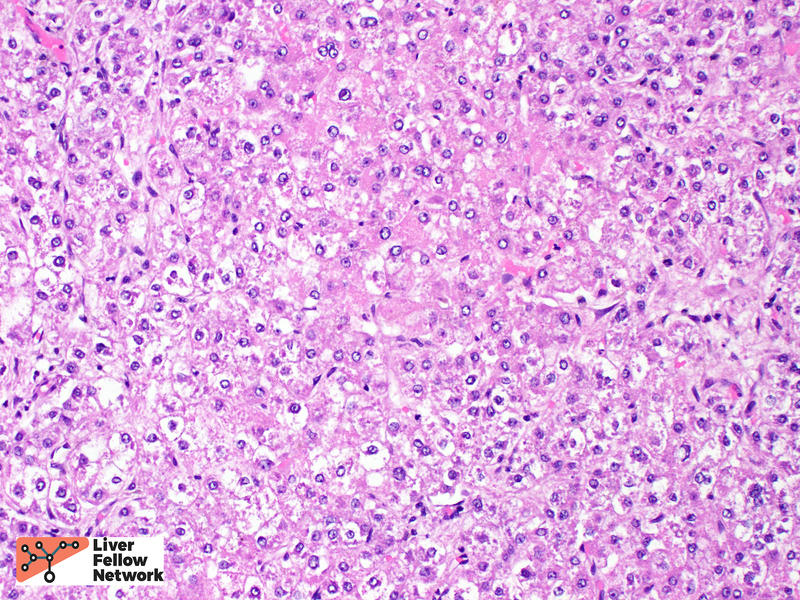

The most common architectural patterns are solid, trabecular (in which tumor cells grow in thickened hepatic plates separated by sinusoidal spaces), and acinar/pseudoglandular patterns (in which the tumor cells form small nests with central degeneration that resembles glands), Figure 7. However, the poorly differentiated HCCs will often grow as solid masses and will not resemble normal hepatocytes (Figure 8).